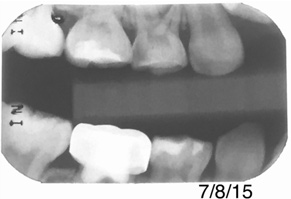

Figure 15 shows bitewings of an 11-year-old boy with high caries risk and history of proximal "kissing lesions" on his primary molars in all four quadrants. He then presented with incipient lesions in his permanent teeth. After resin infiltration (Figure 16), results have been stable for 2 years.

Fig 16. Same patient several months later.

Figure 16